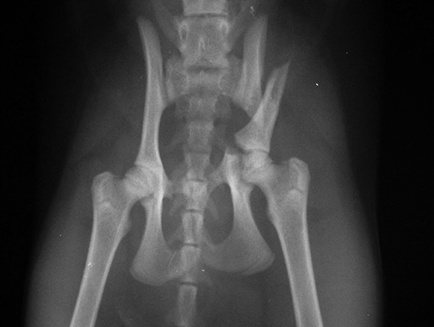

Таза

При переломах таза консервативне лікування розглядається як стратегія лікування частіше, ніж при пошкодженнях в інших областях.

Показаннями для остеосинтезу таза зазвичай є нестабільність або значний зсув кісткових уламків, який може спричинити стеноз порожнини таза. Такі умови створюються при переломах у ділянці кульшової западини, тіла та іноді крила клубової кістки, а також у разі розриву клубово-крижового зчленування. Ці ділянки безпосередньо беруть участь у передачі навантаження з кінцівки на хребет, тому їхнє пошкодження найчастіше потребує хірургічної стабілізації.

Переломи лонних і сідничних кісток оперують рідко, за наявності додаткових обставин, наприклад, у разі пошкодження кістковими уламками органів тазової порожнини). Також важливим критерієм під час обговорення стратегії лікування є час, що минув з моменту отримання травми. Ділянка таза багата на м’язи та інші м’які тканини і має рясне кровопостачання, що стимулює активне утворення сполучної тканини в ділянці пошкодження. Тому у пацієнта, який отримав перелом таза 10-15 днів тому, іноді приймається рішення не оперувати, навіть якщо спочатку хірургічне лікування переломів у собак було показано, оскільки на цих термінах операція більш травматична і не має достатньо переваг перед консервативним лікуванням.